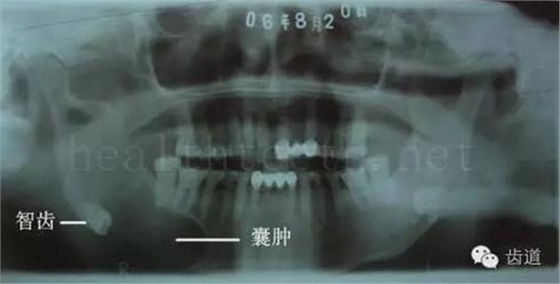

因?yàn)楸旧聿桓阏衬げ。占降牟±邢?,大多是同事收?/span> 頰粘膜扁平苔蘚 舌粘膜扁平苔蘚 舌緣創(chuàng)傷性潰瘍 長期戴活動義齒不當(dāng)或是戴不良修復(fù)義齒造成的口腔粘膜潰瘍,應(yīng)該引起高度警惕,因?yàn)檫@種潰瘍?nèi)菀装┳?/span> 黑毛舌 舌息肉,該患者同時伴有胃、食管息肉,后來看內(nèi)科了,具體情況不詳 四、孩子的牙齒問題 乳牙未退,牙根穿出牙齦對上唇粘膜造成刺激 乳牙滯留,也是孩子在退牙過程中最容易遇到的問題 五、牙齒發(fā)育上的問題 變色牙 氟斑牙 釉質(zhì)發(fā)育不全 四環(huán)素牙 牙神經(jīng)治療后的牙齒變色 10歲孩子剛剛萌出的牙齒變色 2、埋伏牙 左上乳3滯留,恒3未見萌出,曲面斷層片顯示牙齒埋伏 通過CT片確定埋伏牙齒具體的位置,顯示距離左側(cè)上頜竇很近,偏唇側(cè),這為手術(shù)定位提供了方便 手術(shù)中切斷、完整拔出,未損傷上頜竇 其他埋伏牙 3、多生牙 病例1 病例2 病例3,同時多生兩顆牙齒 4、各種畸形牙 畸形過小牙 融合牙:恒牙和乳牙都可以發(fā)生融合的情況(兩顆牙齒長在了一起) 畸形中央尖:在牙齒的中央,兩個牙尖之間又多長出一個牙尖,由于進(jìn)食的磨耗很容易造成磨穿,神經(jīng)就會與外界相通,出現(xiàn)牙髓炎的癥狀 六、牙齒的外傷 牙冠折斷 牙根折斷 烤瓷牙打樁修復(fù)后牙根折斷 外傷后牙齒的全脫位,應(yīng)該保留牙齒盡早做再植手術(shù) 七、牙齒的慢性損傷 牙頸部楔狀缺損 牙冠劈裂及完整拔除后的情況 牙根縱裂及拔除后的情況 牙隱裂,牙齒表面有肉眼看不到的裂紋,細(xì)菌通過其進(jìn)入牙髓,容易出現(xiàn)牙髓炎癥狀,嚴(yán)重可以造成牙齒的劈裂 這是一位來中國學(xué)習(xí)的俄羅斯大學(xué)生的牙齒,已經(jīng)做過了根管治療,牙齒咬合面有隱裂,通過鋼絲結(jié)扎固定,做鑄造金屬冠修復(fù)。 八、牙髓炎、根尖周炎 下面圖片都是慢性根尖周炎的病例,有了齲齒,進(jìn)一步發(fā)展就是牙髓炎,如果此時沒有得到及時的治療,疾病會逐漸發(fā)展破壞到根尖的骨質(zhì),將骨質(zhì)破壞后就在牙齦上出現(xiàn)一個膿瘺,此時患者不再感覺到牙齒的疼痛了,往往忽視了治療,但是這種不痛并不是疾病好轉(zhuǎn)了,而是因?yàn)榧膊〉难仔詽B出得到了引流,這個膿瘺會出現(xiàn)有時候變大了,有時候又變小了,但是如果不治療是不會自己愈合的,只有經(jīng)過完善的根管治療后才有好轉(zhuǎn)的可能,但是在疾病的治療中時間是起決定作用的,時間拖得越晚,好轉(zhuǎn)的可能性越小,經(jīng)過根管治療后如果膿瘺還是沒有消失,就需要做根尖刮治術(shù),如果仍然沒有好轉(zhuǎn),就只能做根尖切除術(shù)了,這對牙齒的穩(wěn)固是不利的。下面圖片中在膿瘺中插入了一個牙膠尖,是我們做根管充填用的材料,是非常軟的,就是在口腔牙齦瘺管的地方插進(jìn)去,通過拍牙片可以清晰地看到它到達(dá)的位置,從而確定發(fā)病的牙齒,此處是為了讓大家看得更清楚。 門牙兩個膿瘺 烤瓷牙修復(fù)后牙齦出現(xiàn)兩個膿瘺,插入牙膠尖,牙片顯示牙膠尖到達(dá)的位置就是根尖炎癥的位置,根尖骨質(zhì)密度降低(發(fā)黑的地方) 牙齒根尖膿瘺,治療前、中、后的圖片對照,完善根管治療后膿瘺明顯消失了 牙髓炎和根尖炎治療的關(guān)鍵就是根管治療 合格的根管充填治療 不良的根管充填治療 九、關(guān)于智齒(第八顆牙) 四顆長不出來的智齒 智齒反復(fù)發(fā)炎造成的頰瘺,膿腫切開引流后面部會留疤 智齒造成的頜骨囊腫,手術(shù)切除后需要植骨 十、各種錯合畸形 開合 深覆合 深覆蓋,上頜前突 反合(地包天) 牙齒排列擁擠 來源:牙醫(yī)愛看的 KQ88口腔醫(yī)學(xué)網(wǎng)